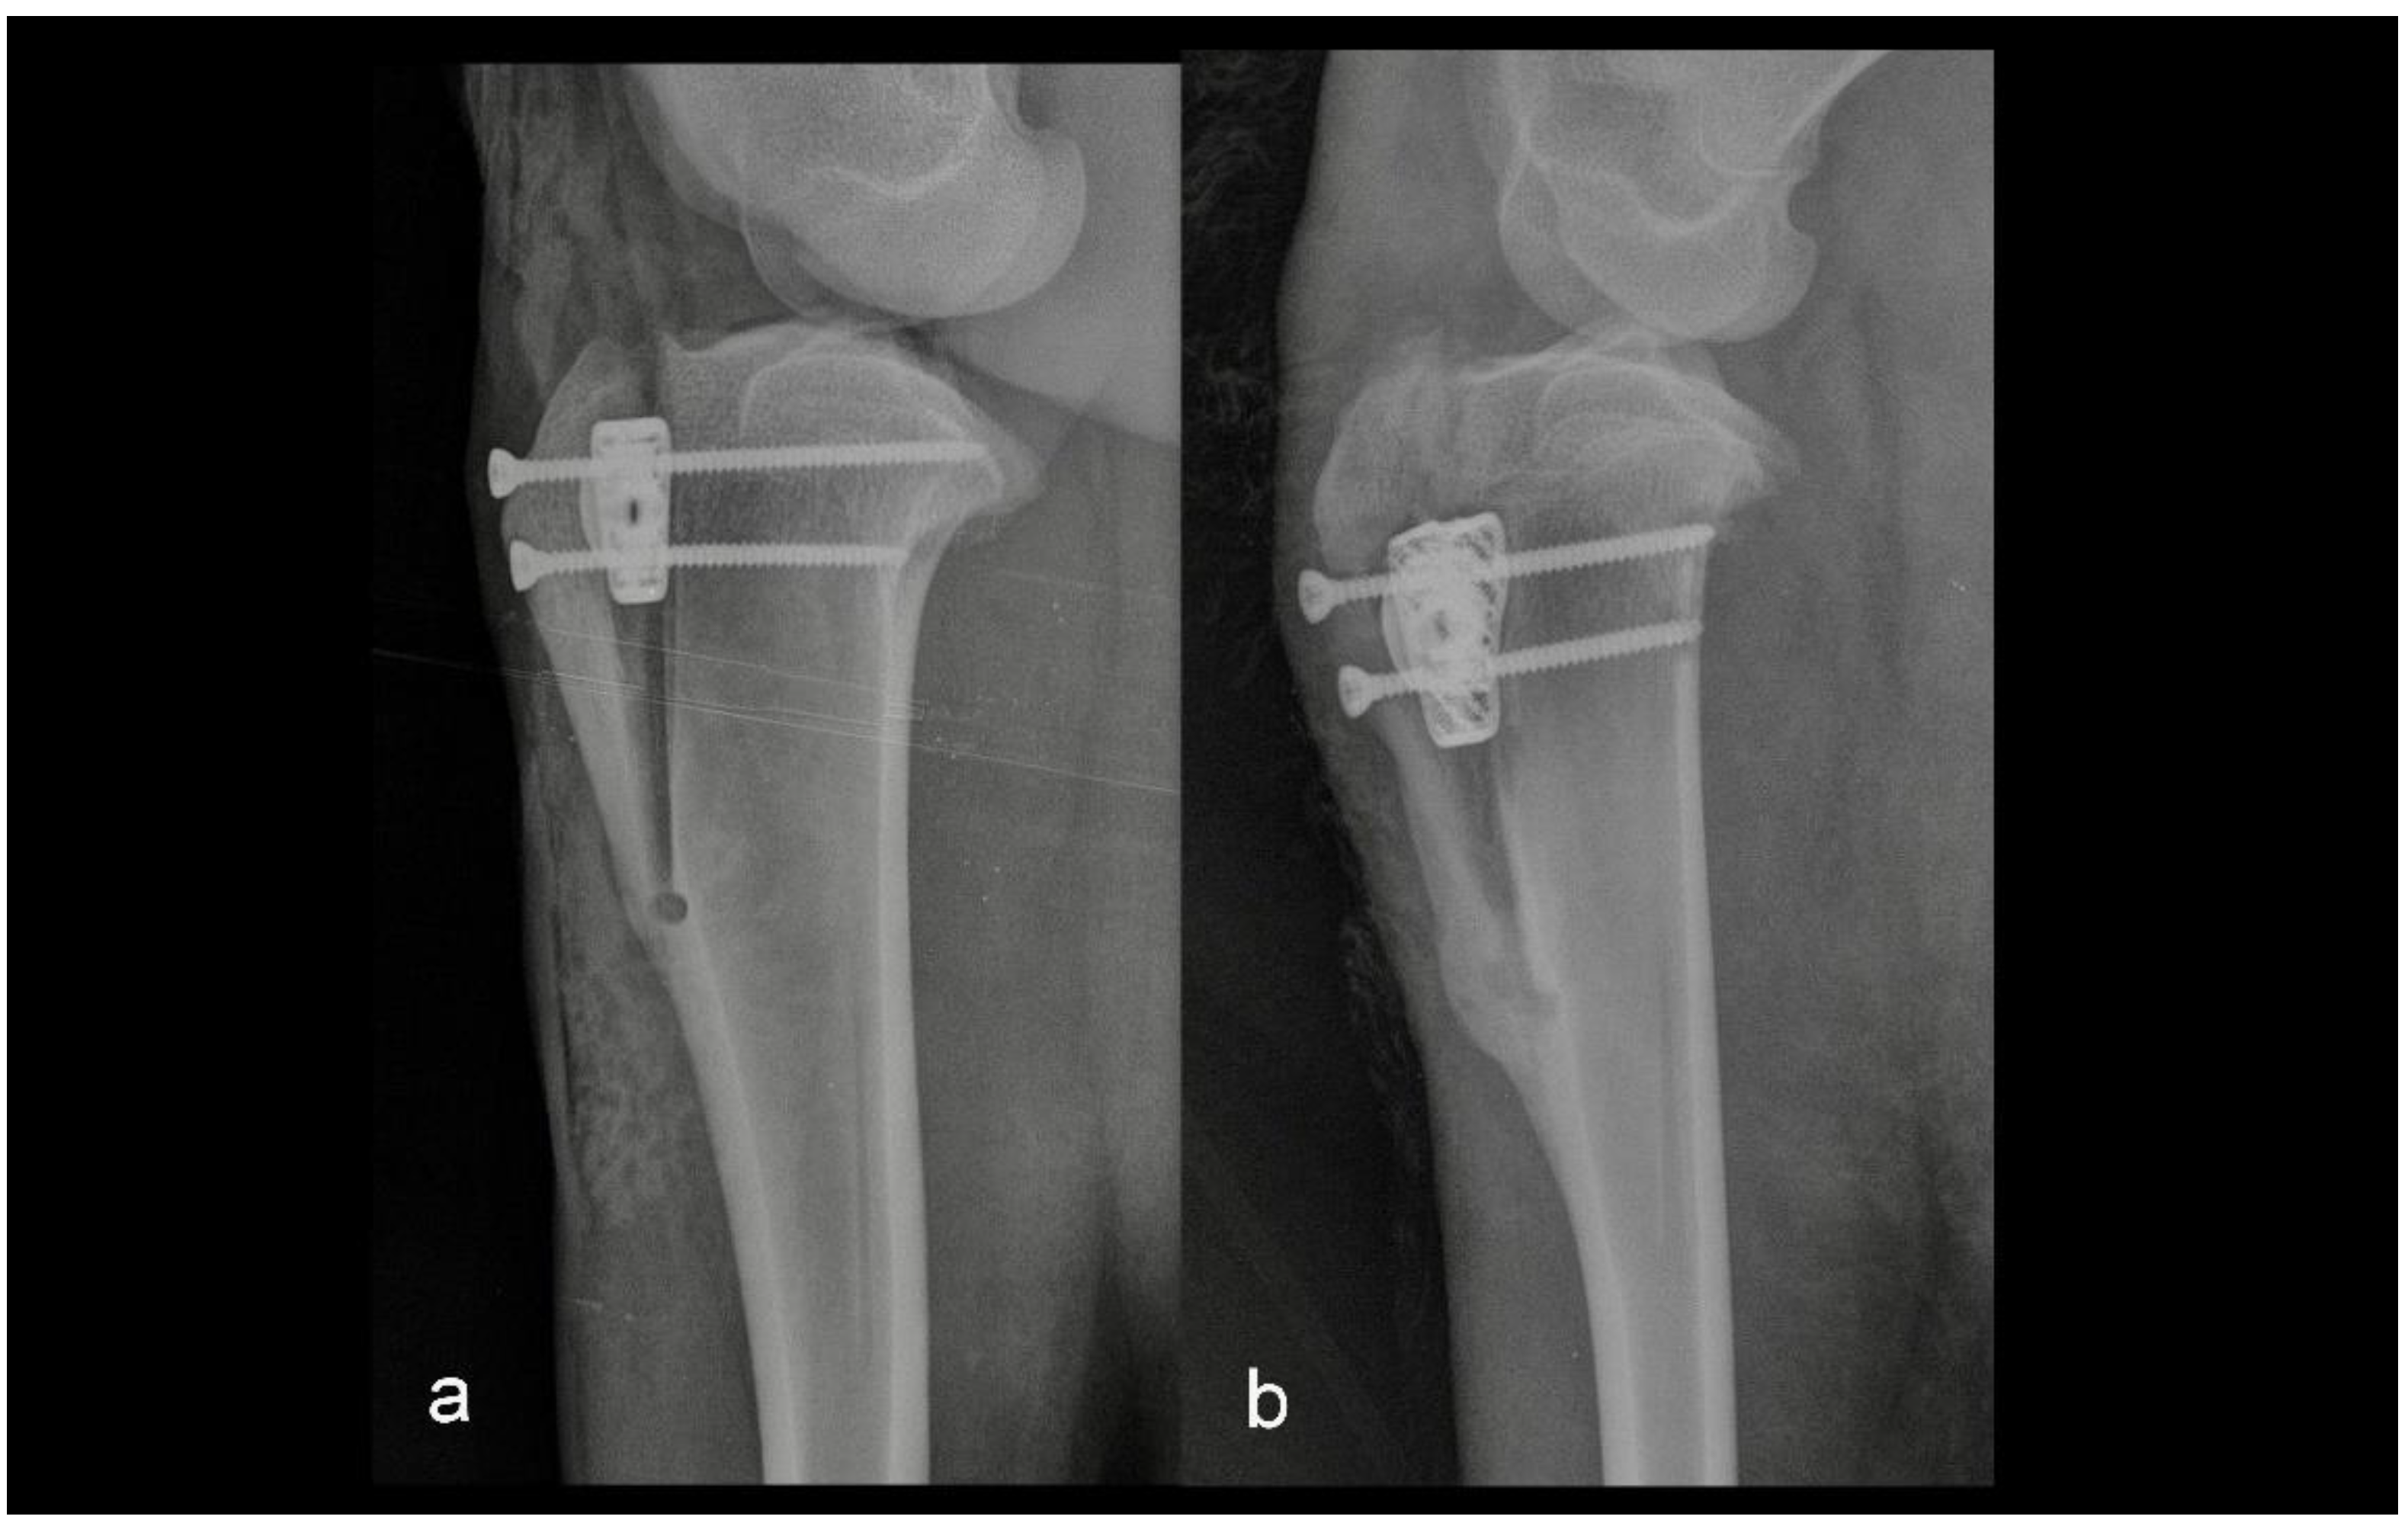

The main purpose of this retrospective biomechanical study was to determine the biointegrity of porous TTA CF cages in the tibia six months after surgery. The other purpose was to compare the loads that were needed to pull the TTA CF cage out in the two groups. The groups were divided retrospectively depending on the postoperative radiographs. The first group consisted of five sheep in which osteotomy and TTA CF cage fixation were performed as assumed preoperatively (Figure 1).

Figure 1. Mediolateral radiograph of the stifle in Group 1 immediately postoperatively (a) and at six months postoperatively (b). Osteotomy and tibial tuberosity advancement were performed as assumed preoperatively.